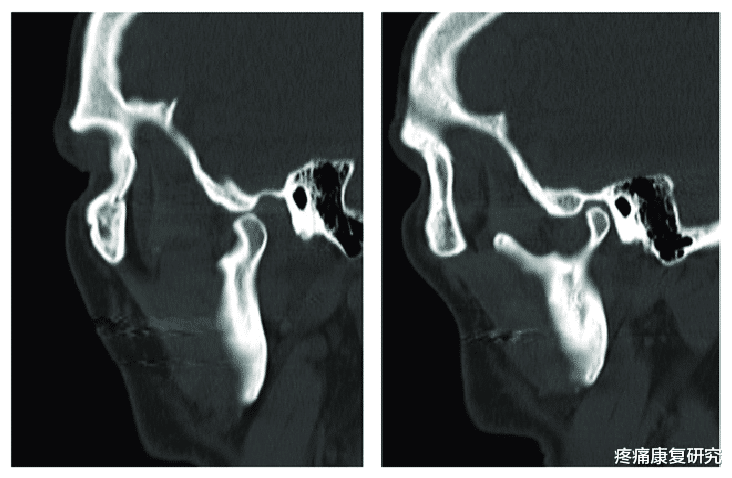

颞下颌关节又称“颞颌关节”或“下颌关节” , 它们是一组在耳朵前面滑动和旋转的关节 。 由下颌骨髁突、颞骨关节面、居于二者之间的关节盘、关节周围的关节囊和关节韧带(颞下颌韧带、蝶下颌韧带、茎突下颌韧带)所组成 。

颞下颌关节是人体最复杂的关节之一 , 这些关节和肌肉一起 , 允许下颌骨上下、左右、前后移动 。

当下颌骨和关节正确对齐时 , 可以进行平滑的肌肉动作 , 如咀嚼、说话、打哈欠和吞咽 。 当这些结构(肌肉、韧带、椎间盘、颌骨、颞骨)在运动中不对齐或不同步时 , 可能会出现一系列问题 。

颞下颌关节紊乱是一种涉及和关节头、颞下颌关节和神经系统的慢性面部疼痛相关的疾病 。 任何妨碍肌肉、骨和和关节之间系统协调工作的问题都会导致颞下颌关节紊乱 。

关节内部紊乱

这些一般是由下颌脱臼或颈椎间盘移位或髁突受伤导致的 。